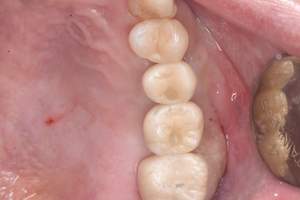

口腔内写真-1

口腔内写真-2

- Befor

- After

| 年齢 | 60代・男性 |

|---|---|

| 主訴 | 左上5番6番 |

| 治療内容 | インプラント埋入 |

| 治療費 | インプラント埋入料 825,000円 ソケットリフト(骨造成) 220,000円 サージカルガイド 66,000円 2次OPE 44,000円 静脈内鎮静麻酔 77,000円 合計 1,232,000円 (2024年1月現在) |

| 治療期間 | 10ヶ月 |

| リスク・副作用 | リスク・副作用 |

| 治療方針 | 左上5番6番目の歯根破折の為抜歯を行いました。その後インプラント埋入を行いました。 |

| 特記事項 | インプラントは人工物なので虫歯になることはありませんが、歯周病(インプラント周囲炎)にはなります。 インプラントを長持ちさせるには、毎日の歯磨きと合わせて、3〜6ヶ月ごとの定期検診でのクリーニングが大切です。 |

| 担当者所見 | 歯を失ったまま放置してしまうと、周囲の歯に負担がかかるため、お口の中全体のバランスが崩れます。 インプラントは、骨に人工の歯根を埋め、被せ物を被せる治療法です。 外科的な手術が必要ですが、健康な歯を削ることなく、天然の歯と同じようにかめるようになります。 |